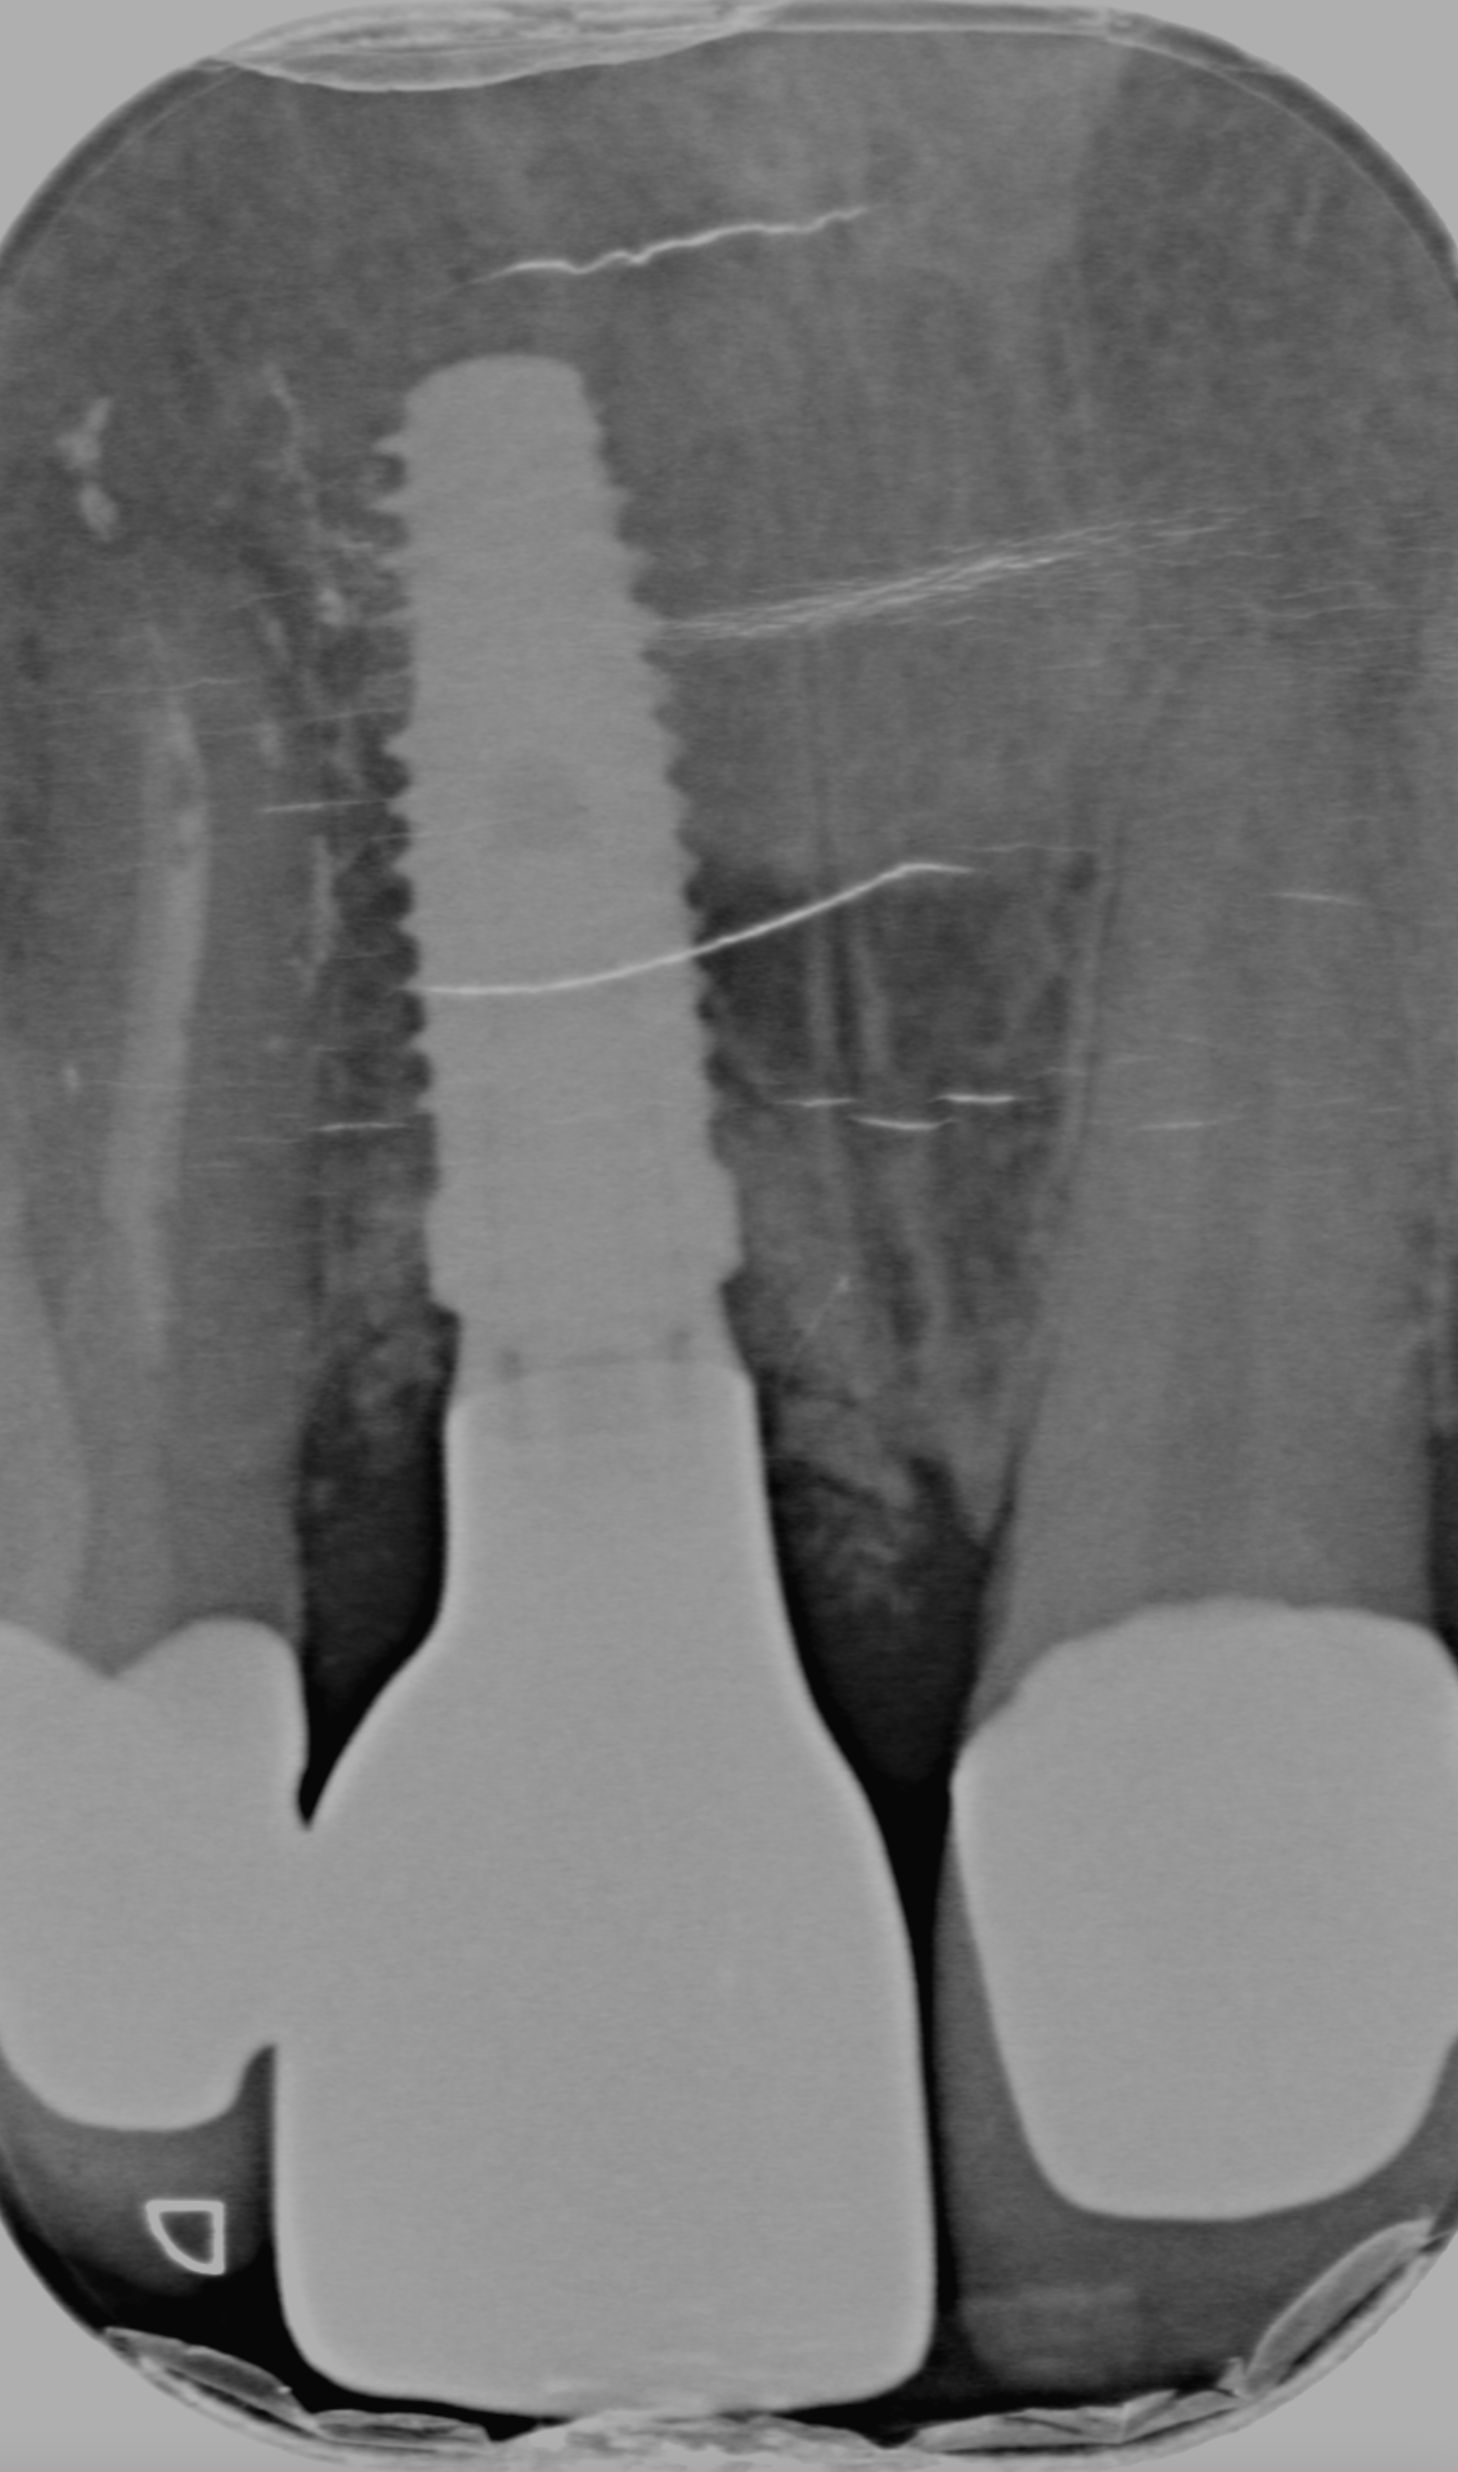

Caso 2

Il paziente, quando era ancora bambino, ha subito un trauma sull’incisivo centrale provocandone la necrosi e interrompendo la crescita completa della radice. Il dente è stato curato e riabilitato in modo tale da mantenerlo in arcata per più tempo possibile. A crescita completa del paziente, a causa dello stato precario dell’elemento dentario, si è proceduto con la sostituzione con un impianto osteointegrato.

PRIMA

DOPO